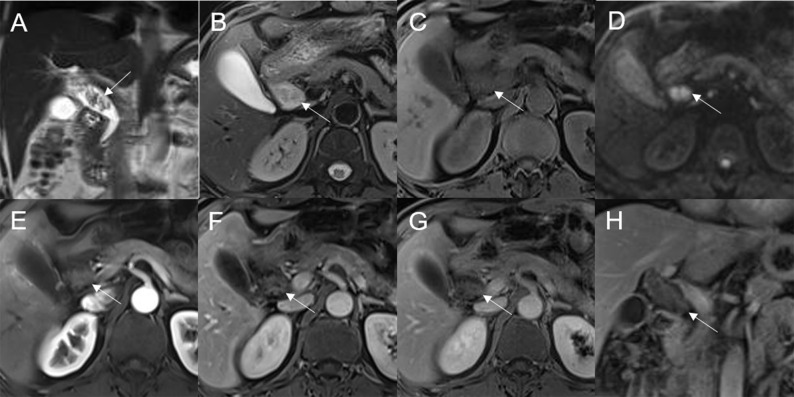

Mean lesion size in the whole sample was 30.83 ± 20.93 mm. All patients presented with an intraluminal ductal mass. While 14/32 (43.75%) lesions presented morphologically as focal eccentric-type masses (f3), 9/32 (28.13%) presented as plaque-like masses, 4/32 (12.50%) as bile duct casting masses, and 5/32 (15.62%) as infiltrative masses. In addition, 8/32 (21.88%) lesions showed a frond-like superficial appearance accompanied by other morphologically categorized appearances other than plaque-like superficial (f4, f5; T2).

Bile duct dilatation upstream of the lesion was present in all cases. Bile duct dilatation downstream of the lesion was present in 6/32 (18.75%) cases (f6) and at the lesion in 24/32 (75%) cases. In 8/32 (25%) cases, there was a stricture in the bile duct lumen at the lesion, along with an enlarged bile duct diameter; while four were cases of bile duct casting masses, the other four were cases of plaque-like masses.

On standard MRI scanning, 24/32 (75%) lesions showed hyperintensity and 9/32 (25%) showed isointensity on T2WI, while 9/32 (28.12%) lesions showed isointensity and 23/32 (71.88%) showed hyperintensity on T1WI. In addition, 3/32 (9.38%) lesions showed speckled hyperintensity on T1WI (f7).

On dynamic enhanced MRI, 14/18 (77.78%) lesions showed moderate enhancement, 2/18 (11.11%) showed obvious enhancement, and 2/18 (11.11%) showed slight enhancement. While 13/18 (72.22%) lesions showed stable and persistent enhancement, 5/18 (27.78%) showed wash-in and wash-out enhancement (T2).

On DWI (b = 800 s·mm-2), 5/32 (15.63%) adenomas showed isointensity (f2) and 27/32 (84.37%) showed hyperintensity. In 2/32 (6.25%) cases, the bile duct wall around the lesion showed hyperintensity on DWI (f8). The mean ADC value of the lesions was 1.65 ± 0.38 × 10-3 mm2·s-1 (T2).